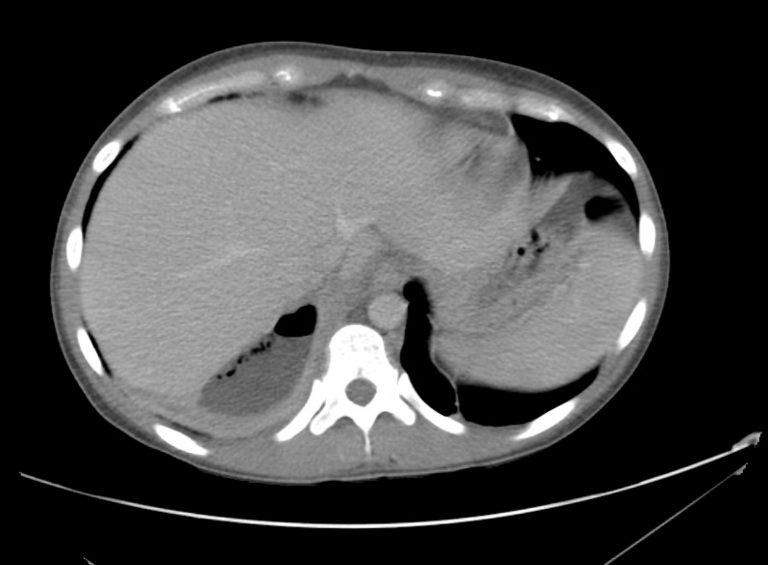

15_pyelo Differential Diagnosis of

from ddxof.com